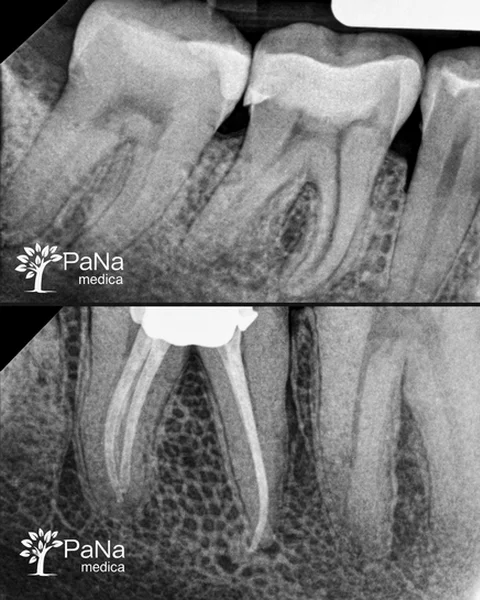

Stomatolog, endodonta / ponad 6 lat doświadczenia

„Zajmuję się leczeniem kanałowym i trudnymi przypadkami. To praca, w której nie ma miejsca na „mniej więcej” — liczy się precyzja i każdy detal.”